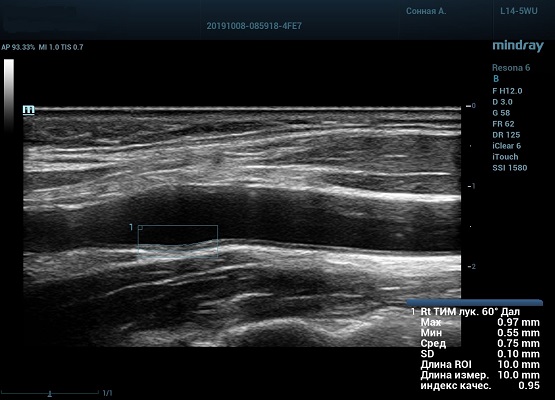

Функция в ультразвуковых аппаратах

На сегодняшний день измерение IMT происходит автоматическим путем при использовании функции AUTO-IMT. Необходимо указать прибору зону интереса, стандартной длиной (1 см), в которой происходит отслеживание кромок и выдача максимального, среднего и минимального значения. УЗИ аппараты компании Mindray среднего, экспертного и премиального класса снабжены данной функцией и позволяют контролировать не только полученные значения, но и оценить точность измерения кромки в конкретной зоне по индексу качества. Используя индекс качества, легко решить, можно ли использовать полученное значение.